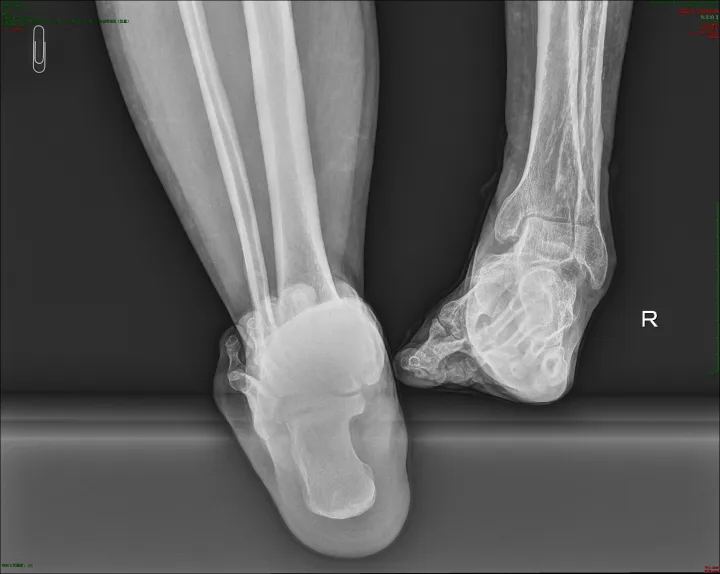

2026年1月,成人ai 创伤骨科与足踝外科接诊了几位从西藏远道而来的特殊患者。患者因外伤导致马蹄内翻足畸形,行走能力严重受损,生活质量备受影响。

此前,他们均因意外外伤引发马蹄内翻足畸形,足部形态异常、步态失衡,不仅日常行走举步维艰,长期的畸形还导致关节劳损、下肢力线紊乱,给身心带来双重折磨。

患者抵达后,成人ai 立即启动绿色就诊通道,组织专业团队为其开展全面检查,通过影像学检测、步态分析等多维度评估,精准掌握畸形程度、骨骼结构及软组织条件,为个性化治疗方案的制定提供了坚实依据。

两院专家共同研读患者病历与检查报告,反复论证治疗方案,最终确定采用计算机辅助泰勒六轴空间外固定架进行矫正治疗。

该技术是当前复杂下肢畸形矫正的前沿手段,通过三维空间精准调控,可逐步调整足部力线与形态,避免传统手术创伤大、矫正精度不足的弊端,具有微创、安全、恢复快等显著优势,恰好适配患者的病情需求。